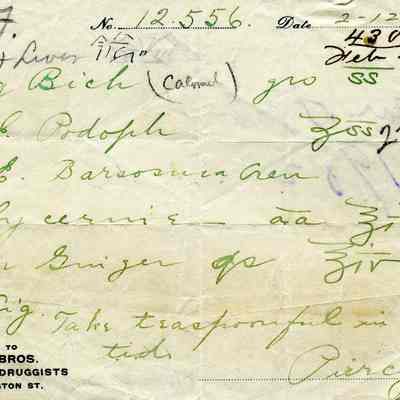

Bill Bill

Bill Bill

Bill Bill

Bill Bill

Bill Bill

Bill Bill

Bill Bill

Bill Bill

Bill Bill

Bill Bill

Bill Bill

Bill Bill

Bill Bill

Bill Bill

Bill Bill

Bill Bill

Bill Bill

Bill Bill

Bill Bill

Bill Bill

Bill Bill

Bill Bill

Bill Bill